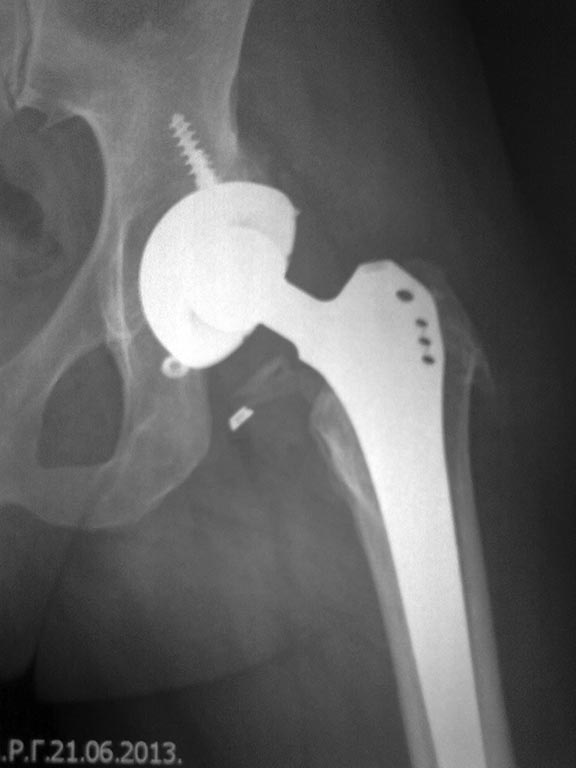

Доброго времени суток уважаемые коллеги , помогите советом.Больная . 38лет гражданин республики Казахстан. Оперирована по поводу коксартроза 8.02.10г операция тотальное эндопротезирование левого тазобедренного сустава. В июле 2012г находясь в гостях в г. Челябинск упала на левый тазобедренный сустав - вывих головки эндопротеза. Попытка вправления под общим наркозом безуспешна и больная направлена по месту жительства, также при поступлении попытка вправить закрыто неудалась(вывих заднее- верхний) и 11.07.12 Произведена операция открытого вправления из доступа Хардинга,в ходе операции с целью восстановления оптимального офсета произведена замена ножки №2 на №3 и головки ХL на М (всего 4 размера).Послеоперационное течение гладкое.Но в октябре 2012г рецидив вывиха, вправлен без особых усилий под в/в наркозом при незначительной тракции по оси и внутренней ротации.В течении 3 нед.проводилось скелетное вытяжение в последующем со слов больной ходила с тростью и все время боялась вывиха.19.06.13г «оступилась» на ровном поверхности ,после чего конечность ротировалась кнутри и стала не опорной.Доставлена к нам. R-грамма т\бедренного сустава от 19.06.13г тотальный эндопротез левого тазобедренного сустава, вывих головки эндопротеза.(ножка в костномозговом канале расположена корректно,остеолизиса нет.А вот откуда взялись заглушки в количестве 3 шт у оперировавшего хирурга выяснить не удалось. В экстренном порядке под общим обезболиванием произведена попытка закрытого вправления . Вывих вправлен, но при незначительной внутренней ротации наступает повторная релюксаци.,Вправлен повторно,наложено скелетное вытяжение за бугристость левой большеберцовой кости, произведен рентген контроль на передвижном аппарате-Вывих устранен ,но обращает внимание выраженая зона отсутствия контакта вертлужного компонента и вертлужной впадины шириной до 4-5 мм от середины крыши и до фигуры слезы.А также остеолизис вокруг винтов. И если на ревизию пойти из Хардинга ,то там будут сплошные рубцы! И удастся ли обойтись головкой на 2 размера длинней.Может быть кто-то менял вертлужный компонент не удаляя ножку из переднего доступа по Лайт-Кегги (Видел видео поверхностного эндопротезирования, они при обработке впадины буржуины ротировали бедро и головку кнутри и вертлужная впадина становилась доступной). Заранее благодарен за совет.

после вправления.